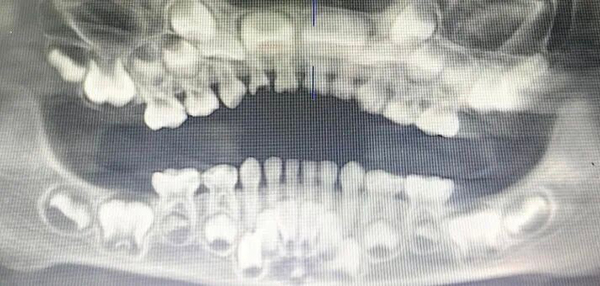

图示:每一颗乳牙下对应一颗恒牙胚,乳牙通常为20颗,其下的恒牙胚未来将替换为28-32颗恒牙。

一旦怀疑迟萌,务必带孩子到口腔科就诊。医生通常会通过拍摄X光片来“透视”颌骨内情况,明确:

·恒牙牙胚是否存在、发育是否正常;

·迟萌的具体原因(如多生牙、囊肿、间隙不足等)。